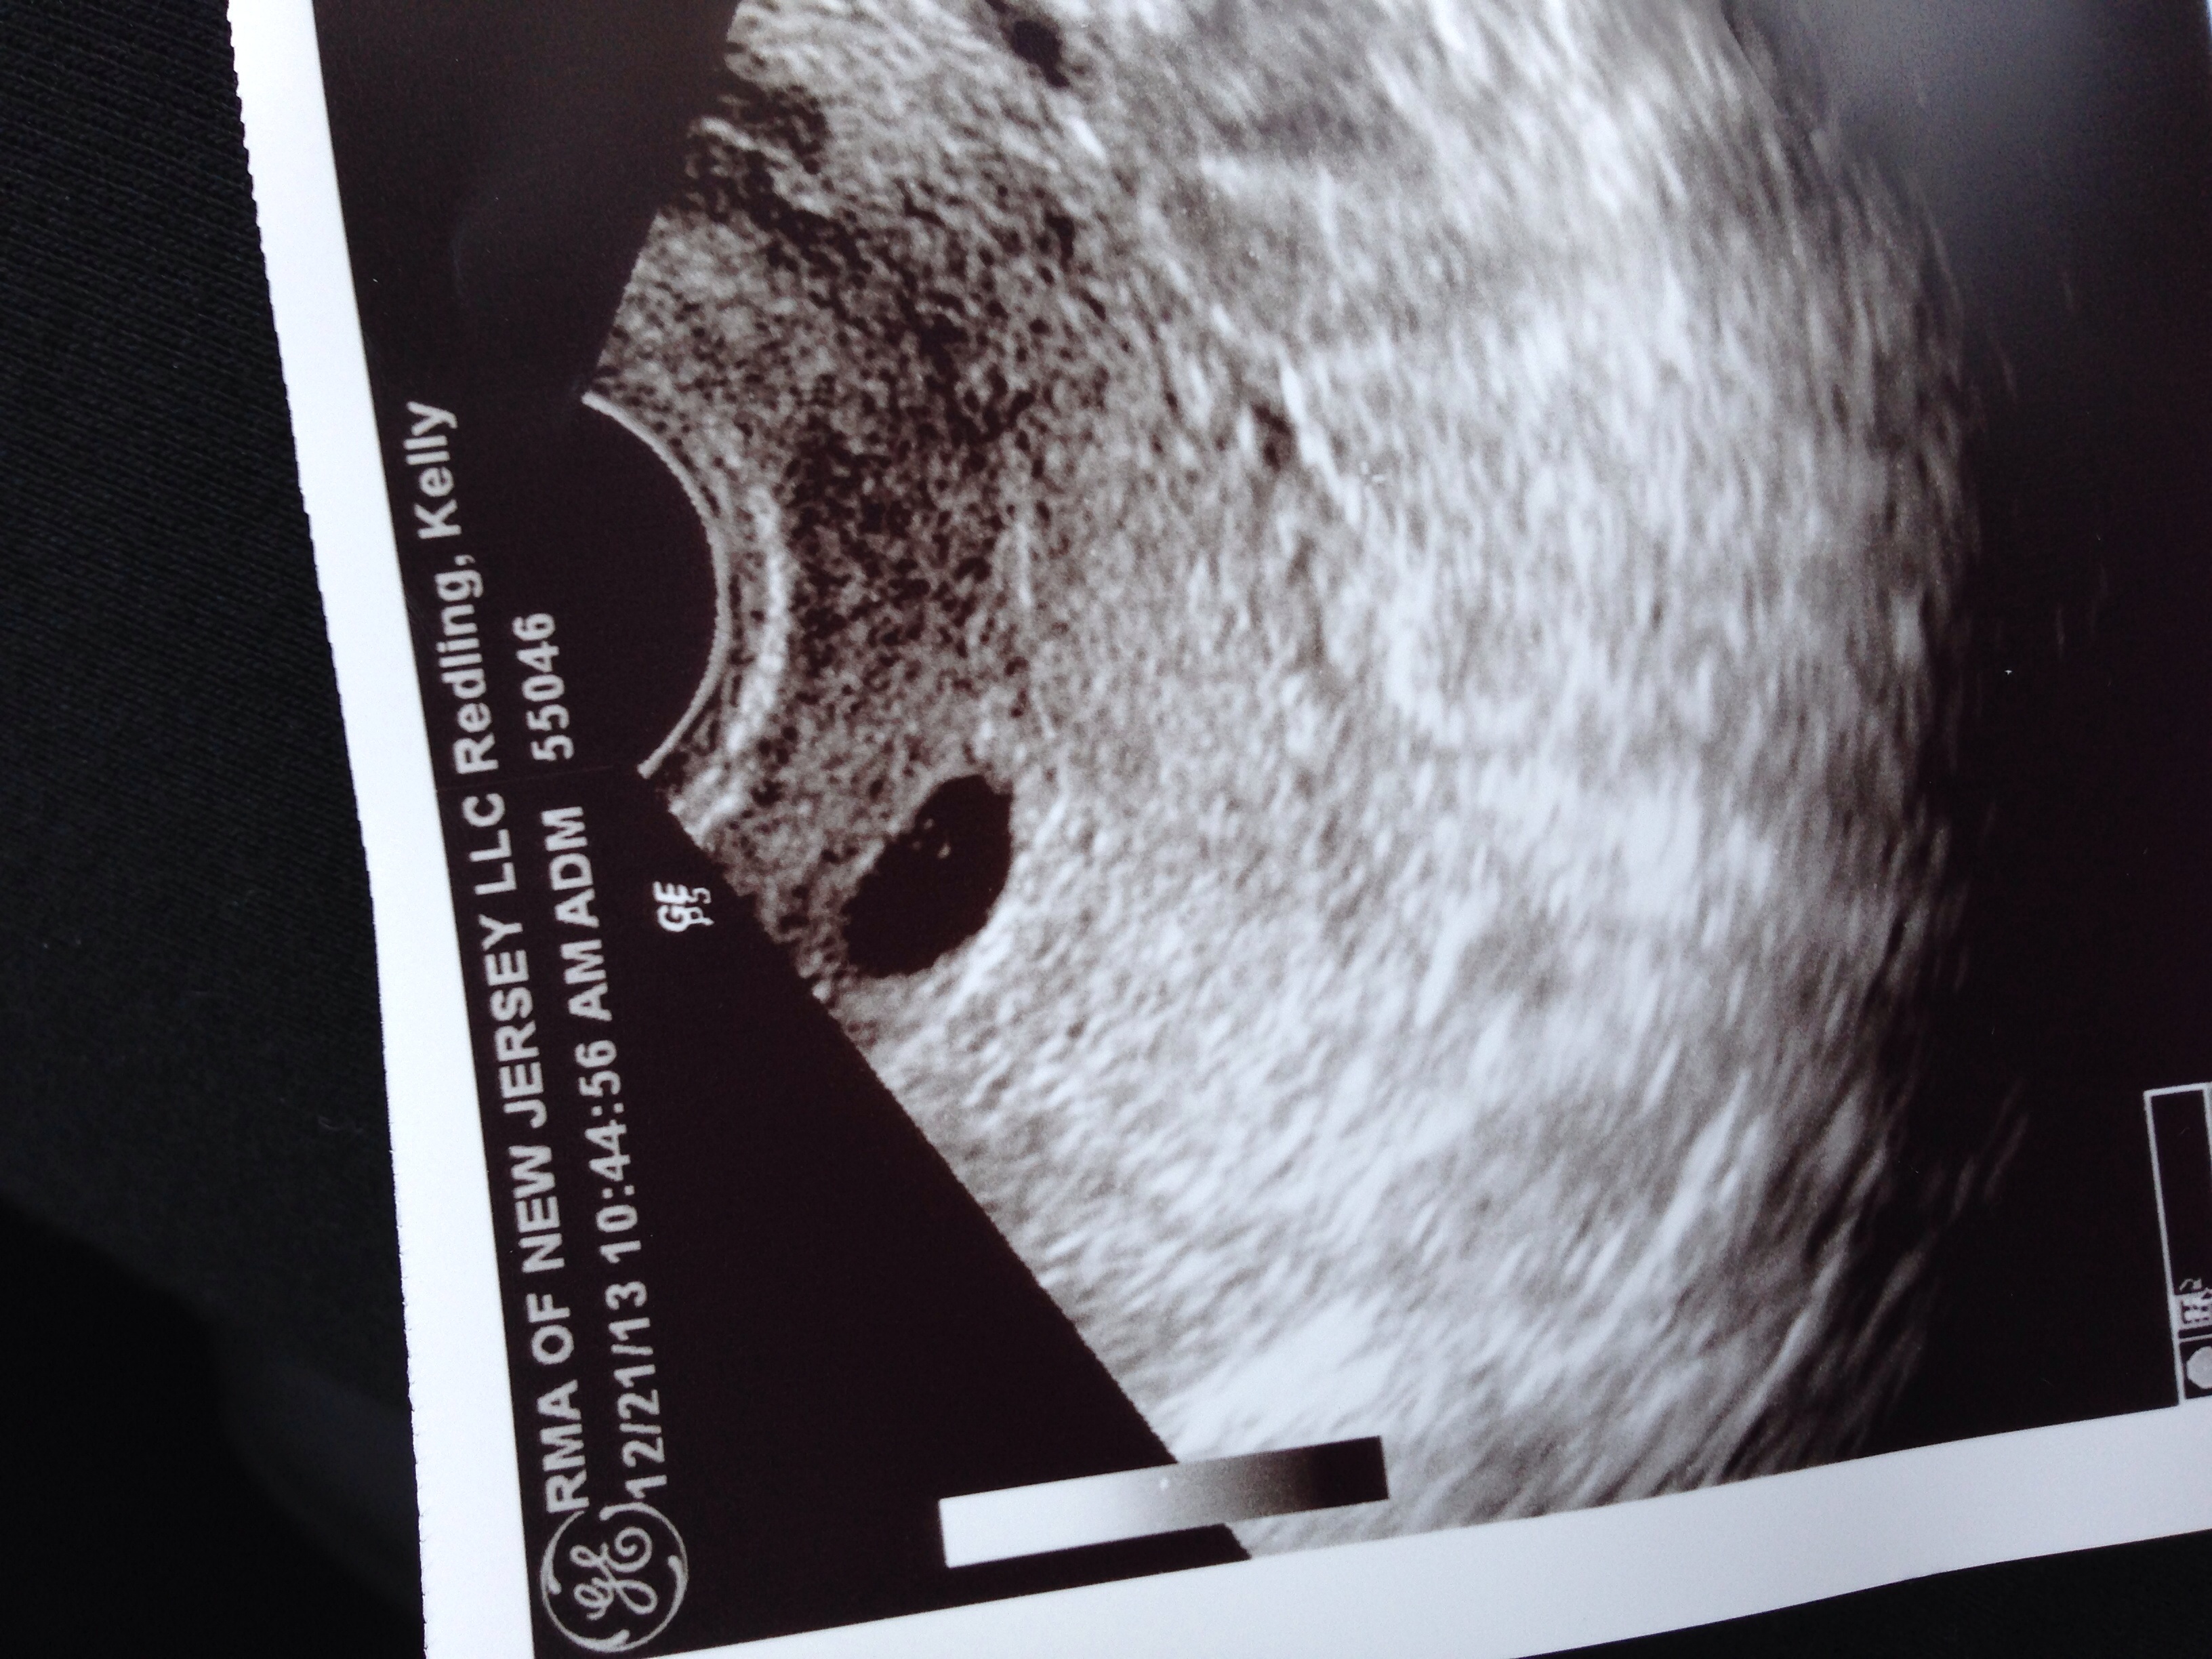

Well I've been here before a few months ago before we lost our LO at 8 weeks last cycle. I wanted to wait till our 1st ultrasound before migrating over! Today we saw 1 beautiful sac and yolk at 5w2d and everything looked great! My beta came back today at 11,248. Little victories! I attached the ultrasound pic below! Funny seeing 3 dots but he only pointed at the 1 dark one in the middle. So don't know what that's about! Next ultrasound is Dec 31st! I will be anxious until the next ultrasound now to hear a heart beat!!

1st U/S- 5w2d Saw yolk sac!